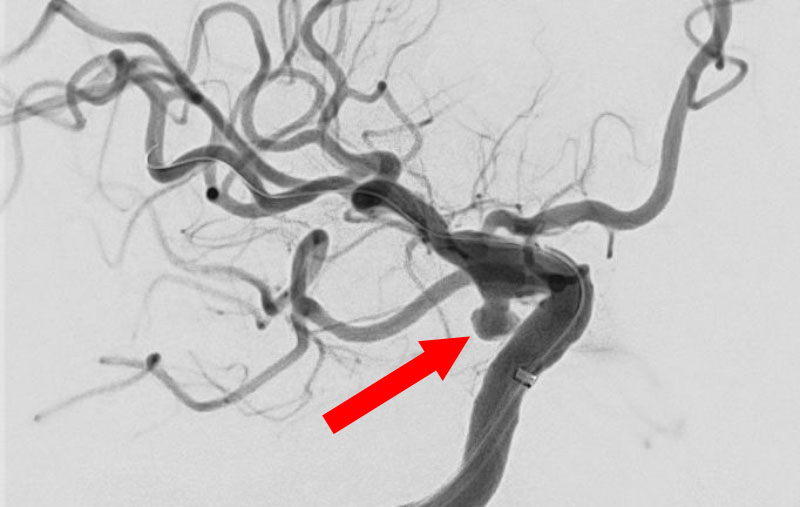

'26年4月

左後下小脳動脈瘤

80代

大阪府の病院

No.1631 手術前

No.1631 手術中

No.1631 手術後